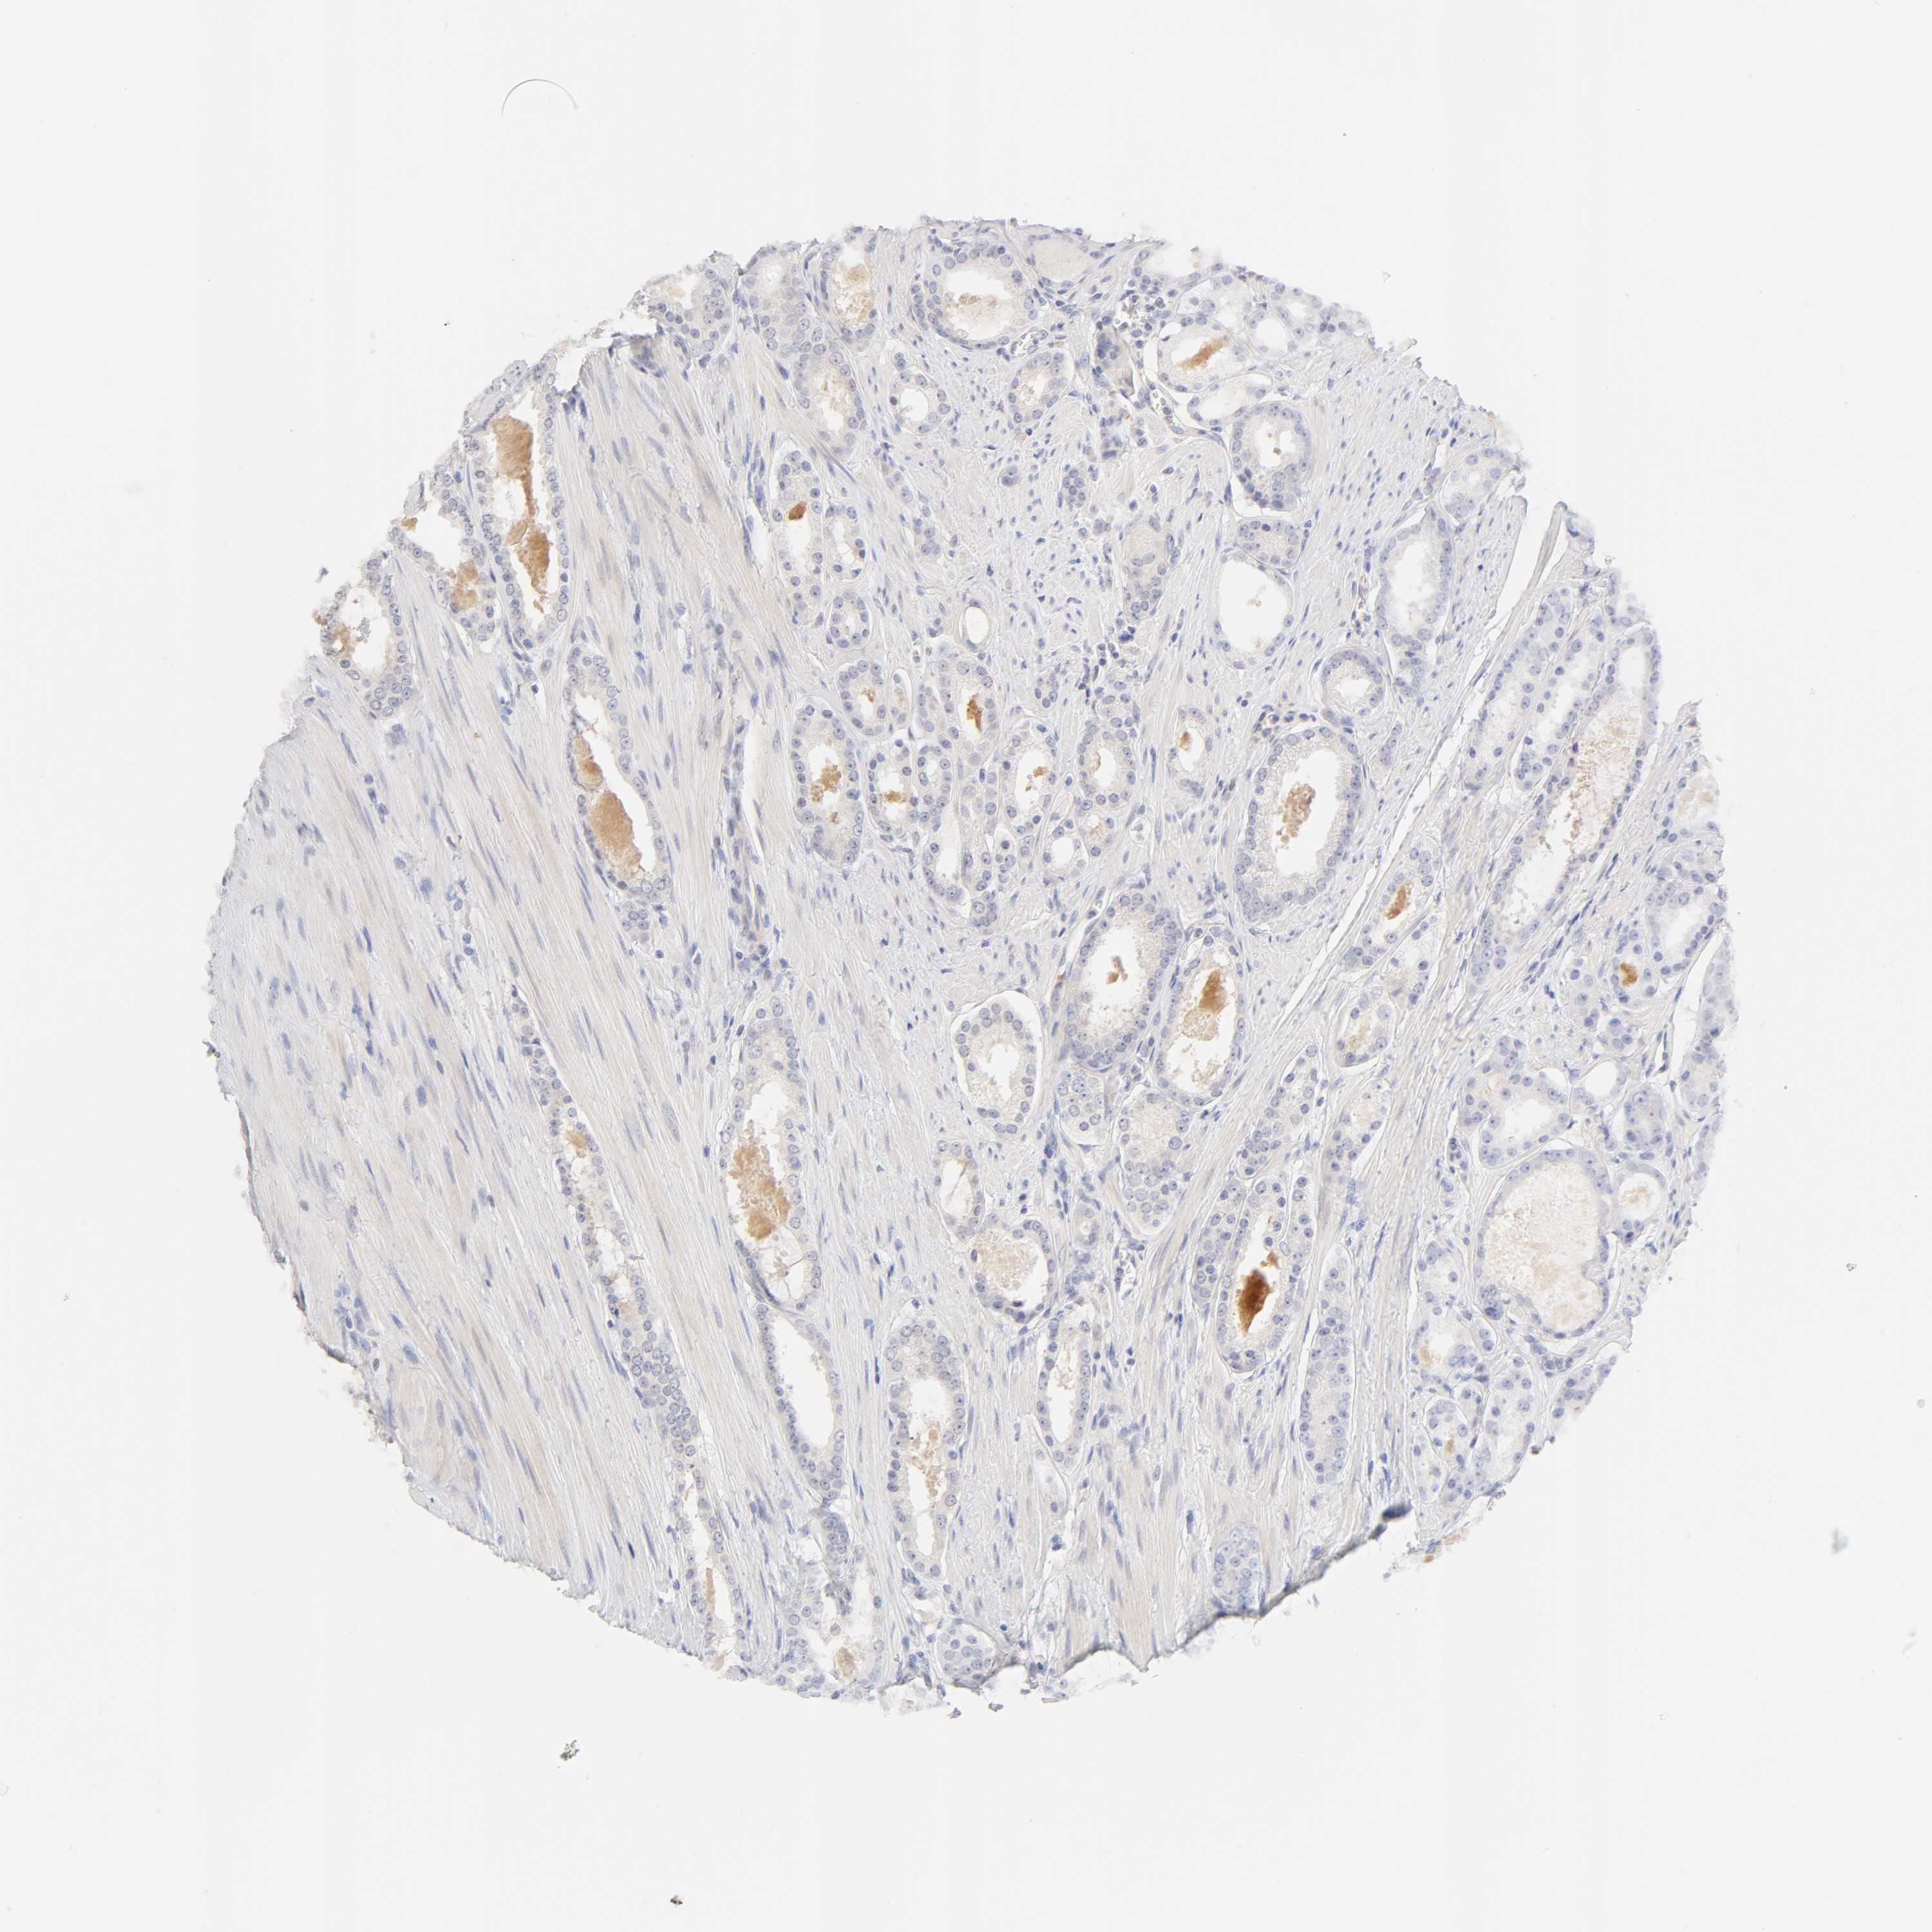

PROSTATE CANCER - Protein expressioni

A mouse-over function shows sample information and annotation data. Click on an image to view it in a full screen mode. Samples can be filtered based on level of antibody staining by selecting one or several of the following categories: high, medium, low and not detected. The assay and annotation is described here.

Note that samples used for immunohistochemistry by the Human Protein Atlas do not correspond to samples in the TCGA dataset.

Antibody stainingi

Antibody staining in the annotated cell types in the current human tissue is reported as not detected, low, medium, or high, based on conventional immunohistochemistry profiling in selected tissues. This score is based on the combination of the staining intensity and fraction of stained cells.

Each image is clickable and will lead to virtual microscopy that enables deeper exploration of all samples and also displays staining intensity scores, fraction scores and subcellular localization as well as patient and tissue information for each sample.

Antibody HPA004331

Staining

High

Medium

Low

Not detected

Intensity

Strong

Moderate

Weak

Negative

Quantity

>75%

75%-25%

<25%

None

Location

Nuclear

Cytoplasmic/membranous

Cytoplasmic/membranous,nuclear

Adenocarcinoma, Low grade

Adenocarcinoma, High grade